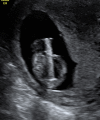

Methods: Retrospective cohort study of all VAS before 14 weeks at two tertiary fetal medicine centres from 2015 to 2018 using a Somatex® intrauterine shunt. All patients with a first trimester diagnosis of megacystis in male fetuses with a longitudinal bladder diameter of at least 15 mm were offered VAS. All patients that opted for VAS after counselling by prenatal medicine specialists, neonatologists and pediatric nephrologists were included in the study. Charts were reviewed for complications, obstetric and neonatal outcomes.

Results: Ten VAS were performed during the study period in male fetuses at a median GA of 13.3 (12.6-13.9) weeks. There were two terminations of pregnancy (TOP) due to additional malformations and one IUFD. Overall there were four shunt dislocations (40%); three of those between 25-30 weeks GA. Seven neonates were born alive at a median GA of 35.1 weeks (31.0-38.9). There was one neonatal death due to pulmonary hypoplasia. Neonatal kidney function was normal in the six neonates surviving the neonatal period. After exclusion of TOP, perinatal survival was 75%, and 85.7% if only live-born children were considered.

Conclusion: VAS in the first trimester is feasible with the Somatex® Intrauterine shunt with low fetal and maternal complication rates. Neonatal survival rates are high due to a reduction in pulmonary hypoplasia and the rate of renal failure at birth is very low. VAS can be safely offered from the late first trimester using the Somatex® intrauterine shunt.